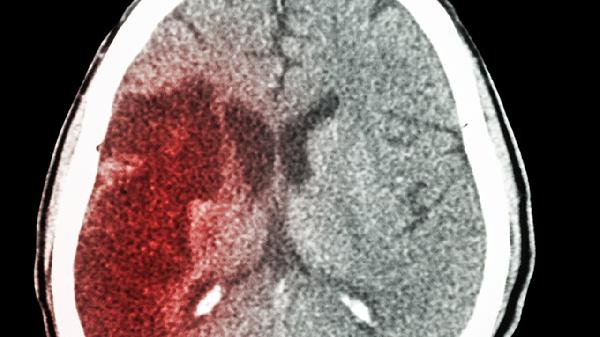

脑出血后肢体无知觉可通过使用神经保护药物、改善脑微循环药物、营养神经药物、抗血小板聚集药物及康复训练等方式治疗。脑出血导致肢体无知觉通常与出血部位压迫神经传导通路、脑水肿加重神经损伤、血肿占位效应等因素有关。

脑出血患者肢体功能恢复需要药物与康复相结合。家属应协助患者定时翻身预防压疮,保持肢体功能位避免关节畸形。饮食需保证优质蛋白摄入促进组织修复,控制钠盐摄入维持血压稳定。康复训练需循序渐进,定期复查头部CT观察血肿吸收情况,出现新发麻木或肌力下降需立即就医。